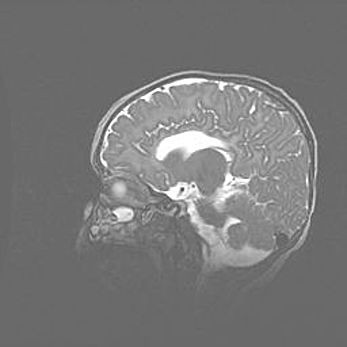

Мальформация Денди-Уокера. Киста задней черепной ямки.

Агенезия мозолистого тела.

Возраст: 2,5 месяца

Вес: 2420 г

Пол: женский

Окружность головы: 37 см

Срок гестации: 32 недели

Мальформация Денди—Уокера — редкий вид патологии ЦНС, представляющий собой врожденный порок развития каудального отдела ствола и червя мозжечка, ведущий к неполному раскрытию срединной (Мажанди) и латеральных (Лушка) апертур IV желудочка мозга. Для этогно синдрома характерна триада симптомов: гипотрофия червя мозжечка и/или полушарий мозжечка, кисты задней черепной ямки, гидроцефалия различной степени. В 70% случаев порок сочетается и с другими аномалиями головного мозга, в частности с агенезией мозолистого тела.